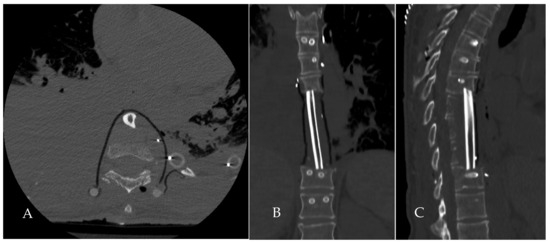

2.4. Surgical Procedure

2.5. Reconstruction